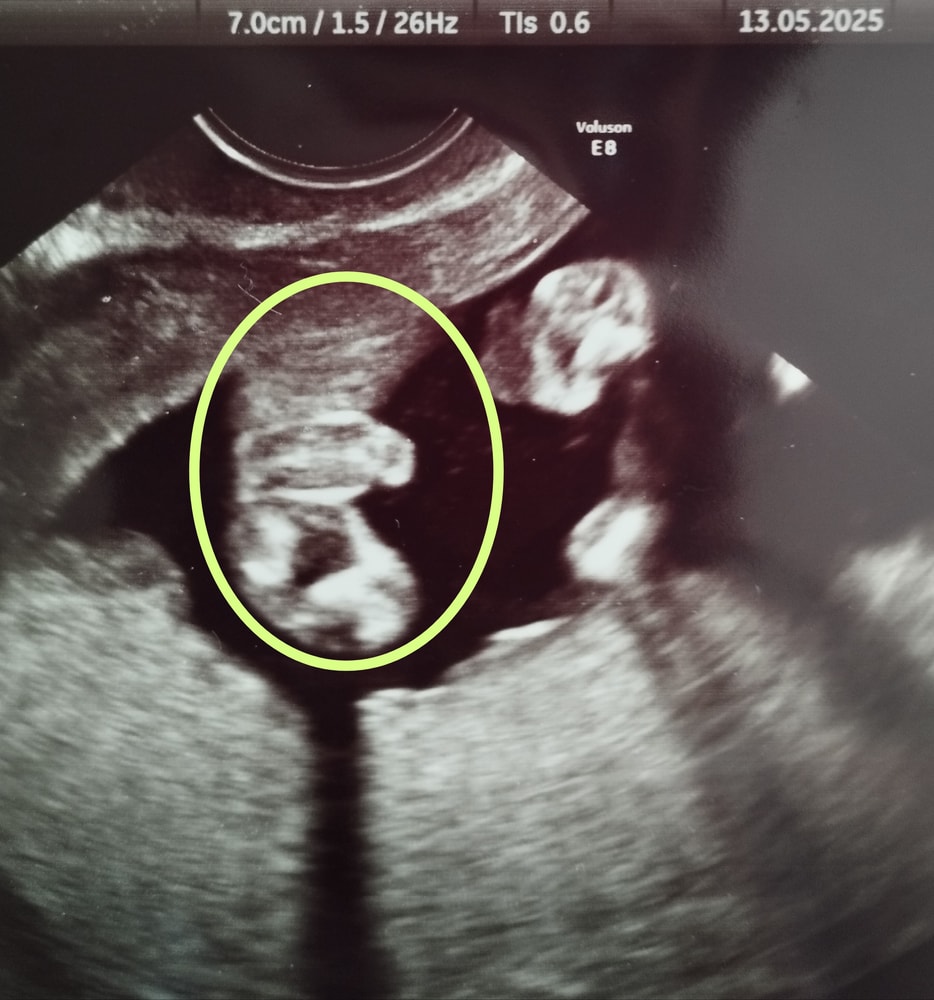

Пол в 15 недель и 5 дней

Вчера была на УЗИ цервикометрии и решили определить с врачом пол, если получится. Дак вот врач говорит, что мальчик))) в прошлые беременности мне монитор не показывали, поэтому не знаю, как выглядит всё это у деток))) Правда, определяли тогда на сроке 20 недель на скрининге, а сейчас вот решила платно сходить заодно с цервикометрией. Как думаете, на таком сроке могут женские органы быть ещё вытянутыми?)))

на фото у вас как-то неоднозначно)) вроде и торчит что-то))) у меня в эту Б с девочкой в 15.5 ничего уже не торчало) На фото было вот прям кофейное зернышко. А с пацанами было прям четко видно уже что пацан и не было вот этих трех полосочек. А тут у вас кофейное зернышко тоже видно… но при этом торчит что-то 🙈😅

Есть Дочки Родила за пять дней до пдр Сыночка

Алена, вот и я сначала не понимала что к чему)))) но на мониторе во время УЗИ врач мне показывала пипку вроде как с других ракурсов, но вот не знаю, как с девочками это выглядит)))

Точно мальчик

На 2 скрининге подтвердили, всё очень хорошо визуализировалось